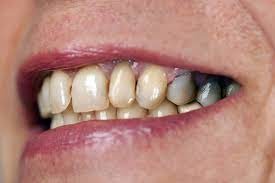

What Causes The Dark Line On My Gums?

You have seen smiles that you know have dental crowns in the front. You look at them and say to yourself that something is not natural. Many times, it is the dark rim of gum tissue that gives it away. The dark rim of gum tissue does not occur around natural teeth, only around teeth that have been covered with dental crowns.

The dark line is associated with an old porcelain dental crown. This style of dental crown is referred to as a porcelain fused-to-metal dental crown because it uses tooth-colored porcelain on the outside and it uses metal under the porcelain for strength. The dark line originates from the edge of the dental crowns where the porcelain and the metal meet at a knife-edge at the gum line. At the knife-edge, a very thin amount of the metal always shows. One of the illusionary techniques cosmetic dentists have used was to hide the thin dark line under the gum line. Over time, the gum tissue would recede and expose the dark line. In some patients the dark line would show through the gum and make it appear dark as well.

How Do You Get Rid of It?

The only way to eliminate the esthetic problem is to replace the dental crowns. When replacing just one single dental crown in the front, you should expect that it might take more than one try-in of the new dental crown before it is permanently cemented into place. Because your central incisors are the most prominent teeth in the mouth, matching them is the most difficult esthetic challenge. Only the best dental technicians are able to mimic one central incisor tooth next to another.

What Are Some of the Replacement Dental Crowns Like?

Some of the clever ways dentists and dental technicians have been able to mimic natural teeth is through the new advancements in dental materials. New all-tooth-colored ceramic dental crowns are the latest technological advancement cosmetic dentists have to recreate natural teeth. In comparison to porcelain fused-to-metal dental crowns, all-ceramic dental crowns do not contain any metal, thus no dark line can appear.

Some advantages and disadvantages of all-ceramic dental crowns are as follows:

Advantages of All-Ceramic Dental Crowns

High esthetics

Excellent fit

If gum recession occurs, there is no dark line

Disadvantages of All-Ceramic Dental Crowns

Not as strong as porcelain-fused-to-metal dental crowns

Cannot be used in all areas of the mouth.